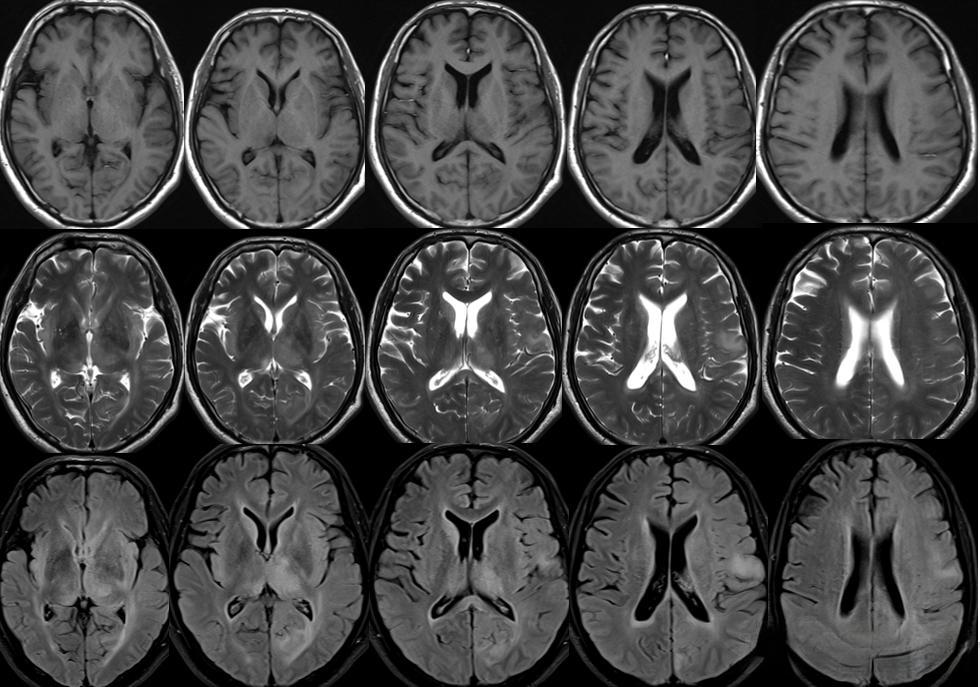

脑内多发异常信号的病变是一种复杂的神经系统疾病,其诊断和治疗都面临着巨大挑战。这种病变通常表现为脑部MRI图像上多个区域出现异常信号,可能由多种原因引起,包括炎症、脱髓鞘、肿瘤等。由于病变的多样性和复杂性,准确诊断往往需要经过一系列详细的检查和排除性诊断。

一个典型的案例可以说明这种病变诊断的复杂性。一位46岁男性患者因头痛、反应迟钝等症状就诊。起初,MRI显示双侧大脑半球多发异常信号,右额叶病灶有占位效应和大片水肿,被误诊为“胶质瘤”。然而,手术后的病理检查结果出人意料,显示为特殊类型的小血管病变,而非肿瘤。随后,患者又经历了多次病情反复和诊断调整,最终被确诊为一种罕见的遗传性脑小血管病——视网膜血管病变伴白质脑病和全身表现(RVCL-S)。

在诊断方面,MRI是最重要的工具之一。典型的MS病灶在MRI上表现为脑室旁、皮层或近皮层、幕下、脊髓等部位的T2高信号灶。增强扫描时,急性期病灶可出现环形或半环形强化。此外,脑脊液检查也是重要的诊断手段,寡克隆区带(OB)阳性可以支持诊断。